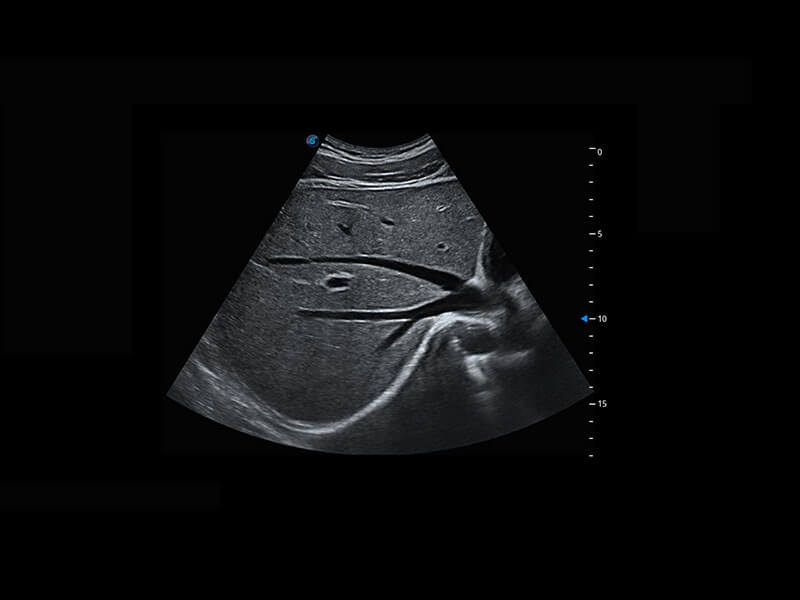

P60優(yōu)異的圖像質(zhì)量搭載??铺筋^,在婦科基礎(chǔ)疾病的診斷、卵泡生長的監(jiān)測、輸卵管通暢情況的判別等方面為您提供生殖應(yīng)用方案。

腔內(nèi)婦科-宮腔分離